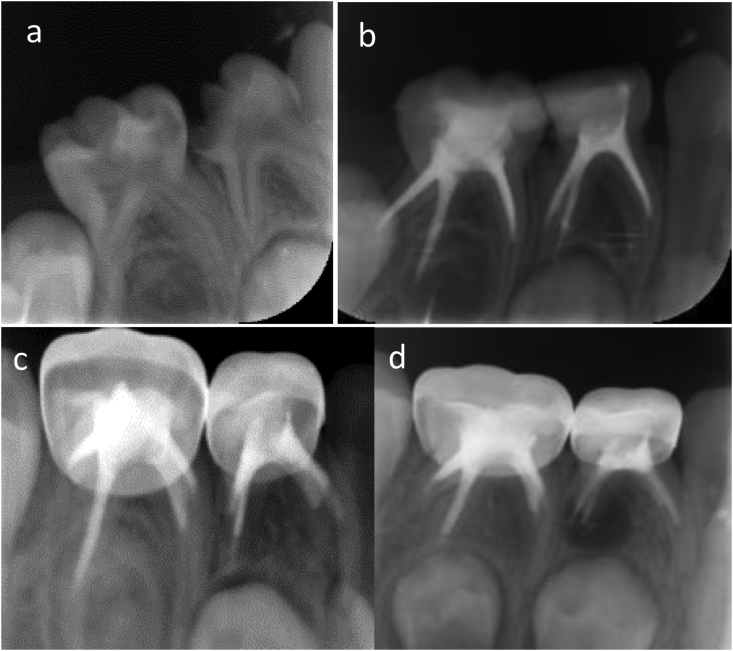

Figure 2.

The right mandibular first primary molar and second primary molar were treated with pulpectomies due to pulpitis caused by caries. a: The radiograph before treatment revealed no periapical radiolucency. b: The immediate postoperative radiograph showed adequate filling in distal root canals and slight underfilling in mesial root canals. c: Twelve months after pulpectomy, radiolucency was seen around the distal root of the first mandibular primary molar. d: Thirty-five months after pulpectomy, the area of radiolucency around the distal root of the first mandibular primary molar became larger, and the second primary molar also showed a periapical lesion around the mesial root. All the pulpectomies failed.